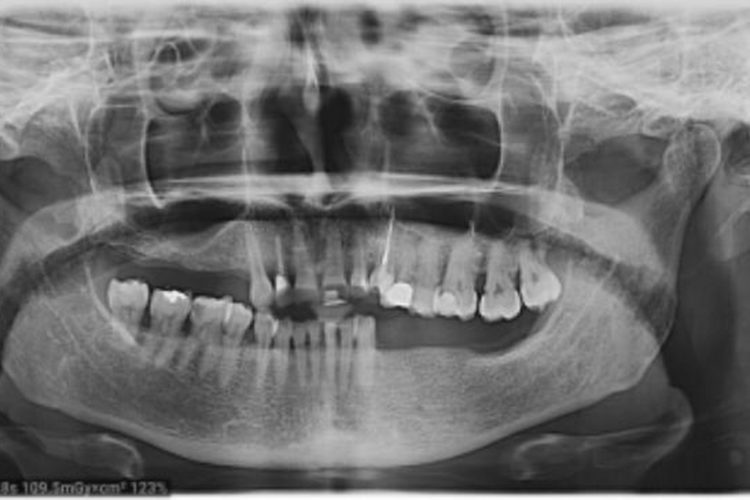

Pacienta in varsta de 52 de ani s-a prezentat in clinica noastra aflandu-se in cursul unui tratament implanto-protetic inceput in alta clinica. Pentru realizarea unor lucrari echilibrate ocluzal i s-a propus si realizat temporizare prin lucrari de PMMA (foto 3 si 4). Dupa 6 luni  s-au  realizat lucrari definitive din ceramica pe zirconiu (foto 5-10).